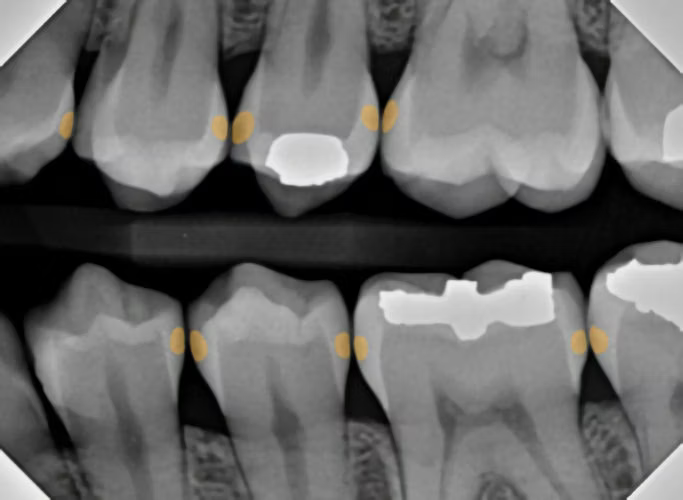

The Catapult Product Evaluation Team, a group of dentists who apply new dental products and innovations into their already active and busy practices, were recently introduced to the DIAGNOcam HD by KaVo. This is a full vision HD camera with three modes. The intraoral mode is similar to most intraoral camera features, but this camera has HD clarity. The two other modes, fluorescence and near-infrared transillumination, are geared more toward diagnosis. The fluorescence mode allows the practitioner to see caries, plaque, and occlusal attrition with greater clarity than with a traditional IO photo. Images in all three modalities can be captured simultaneously and displayed side-by-side.

The transillumination mode, however, for me, was the game changer. The DIAGNOCam’s special tip emits near-infrared light at the gingival level, from both the buccal and lingual aspects. The near-infrared light transmits through healthy enamel toward the camera, which has a corresponding bright, white appearance on the resulting image. Areas of carious or demineralized enamel scatter the light, resulting in a corresponding darker region.

Using the same radiograph from above [Figure 4], I transilluminated the questionable areas, yielding highly accurate discernment of the extent and location of various cavities.